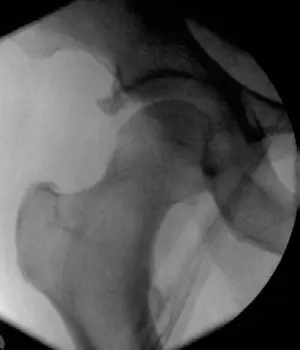

- خلع الورك الخلفي (Posterior Hip Dislocation): الأكثر شيوعًا، يحدث بسبب إصابة لوحة القيادة في حوادث السيارات. الورك يكون في وضعية دوران داخلي وتقريب وثني. خطر إصابة العصب الوركي والنخر اللاوعائي.

- خلع الورك الأمامي (Anterior Hip Dislocation): أقل شيوعًا، يحدث بسبب فرط التبعيد والدوران الخارجي. الورك يكون في وضعية دوران خارجي وتبعيد. خطر إصابة العصب الفخذي.

- خلع الورك الخلفي: الورك يكون في وضعية دوران داخلي، تقريب، وثني.

- خلع الورك الأمامي: الورك يكون في وضعية دوران خارجي، تبعيد، وثني خفيف.